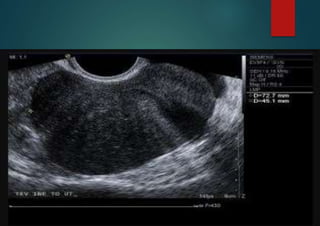

Ovarian Fibroma

most commonly manifest as solid, hypoechoic masses with ultrasound beam attenuation.

As such, they may appear similar to a pedunculated subserosal uterine fibroid